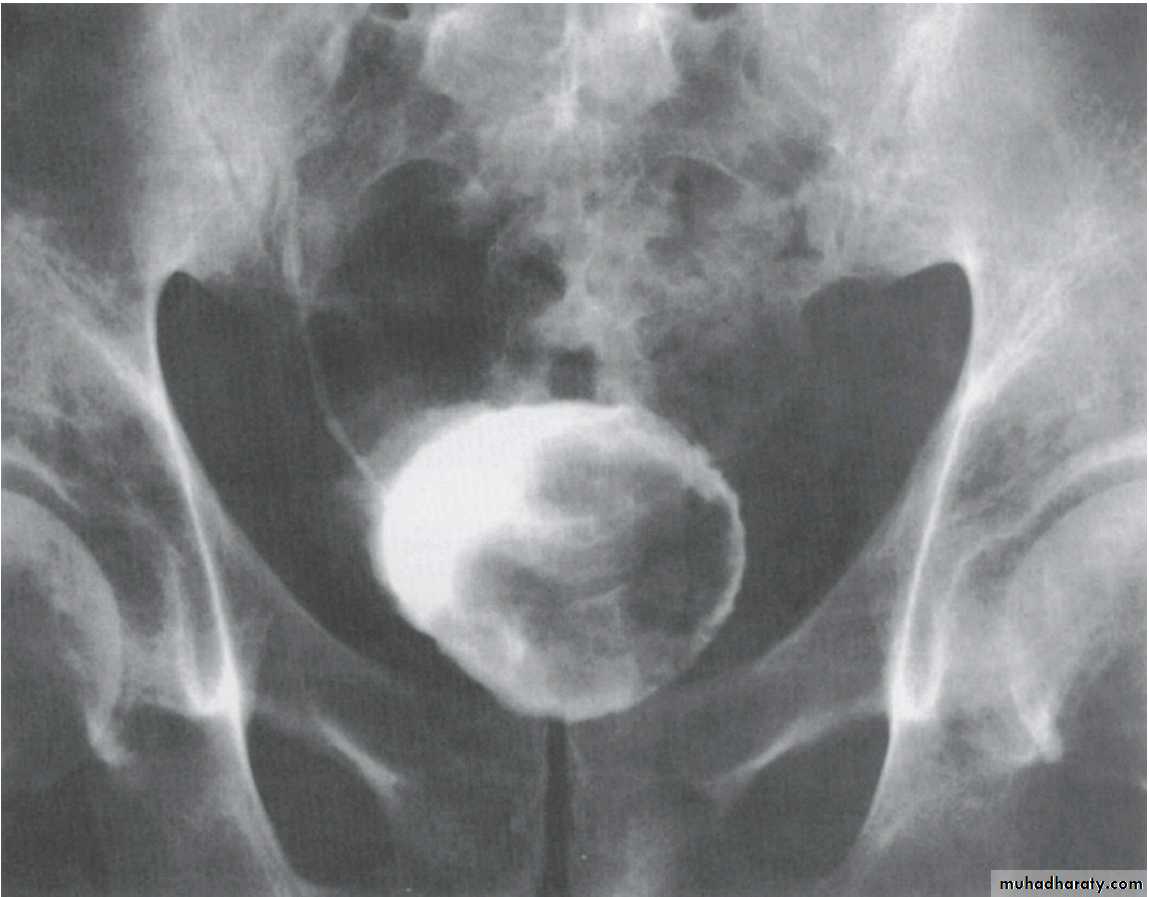

CT scanWHAT IS THE DIAGNOSIS & THE CAUSATIVE ORGANISM ?

Struvite stone ( MAP stone ).Urea splitting microorganisms.

HOW WOULD YOU TREAT HER ?PCNL